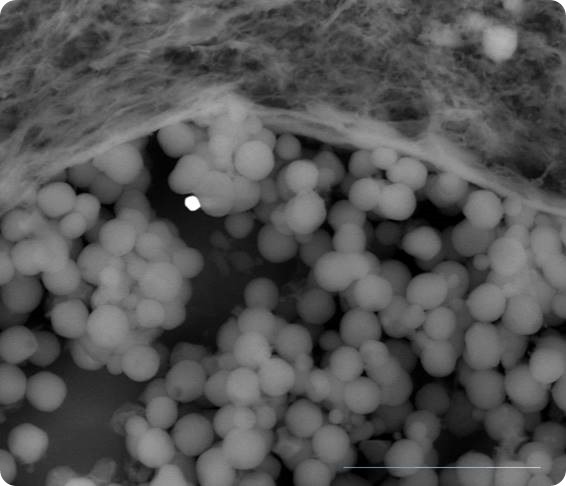

proteic aggregate embedded nanoparticles

A proteic aggregate with embedded spherical nanoparticles. The formation is due to the nanobiointeraction.